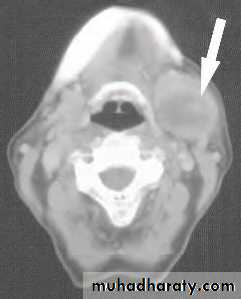

It presents as a slow-growing, painless swellingon examination,it is difficult to differentiate from submandibular lymphadenopathy.

This can be resolved by US examination.

Most salivary neoplasms, even malignant tumours, are often slow-growing, painless swellings. The difficulty is to always distinguish between benign and malignant lesions prior to excision.Pain is not a reliable indication of malignancy

rapid growth, facial nerve palsy, lymph node enlargement and skin tethering are signs of a high-grade malignant lesion.The most common malignant tumour is an adenocystic carcinoma (40%),

InvestigationUS with FNAC/True-Cut biopsy , the investigation of choice ( with carful history 95% of malignancy can be identified)

CT&MRI scanning for preoperative planning.